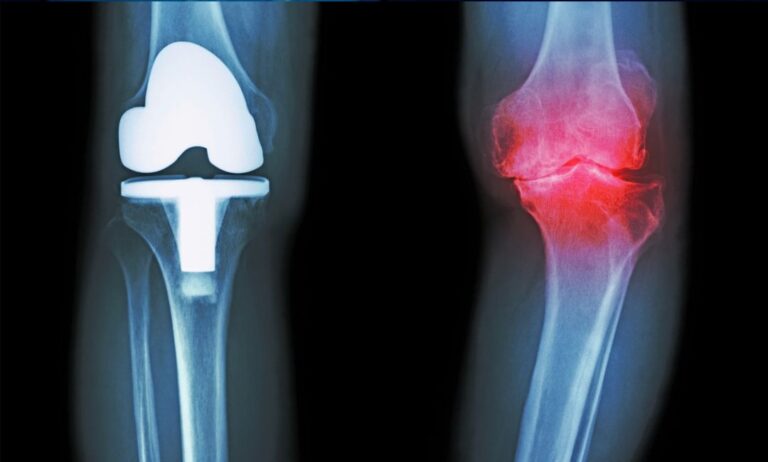

TEP / künstliches Gelenk